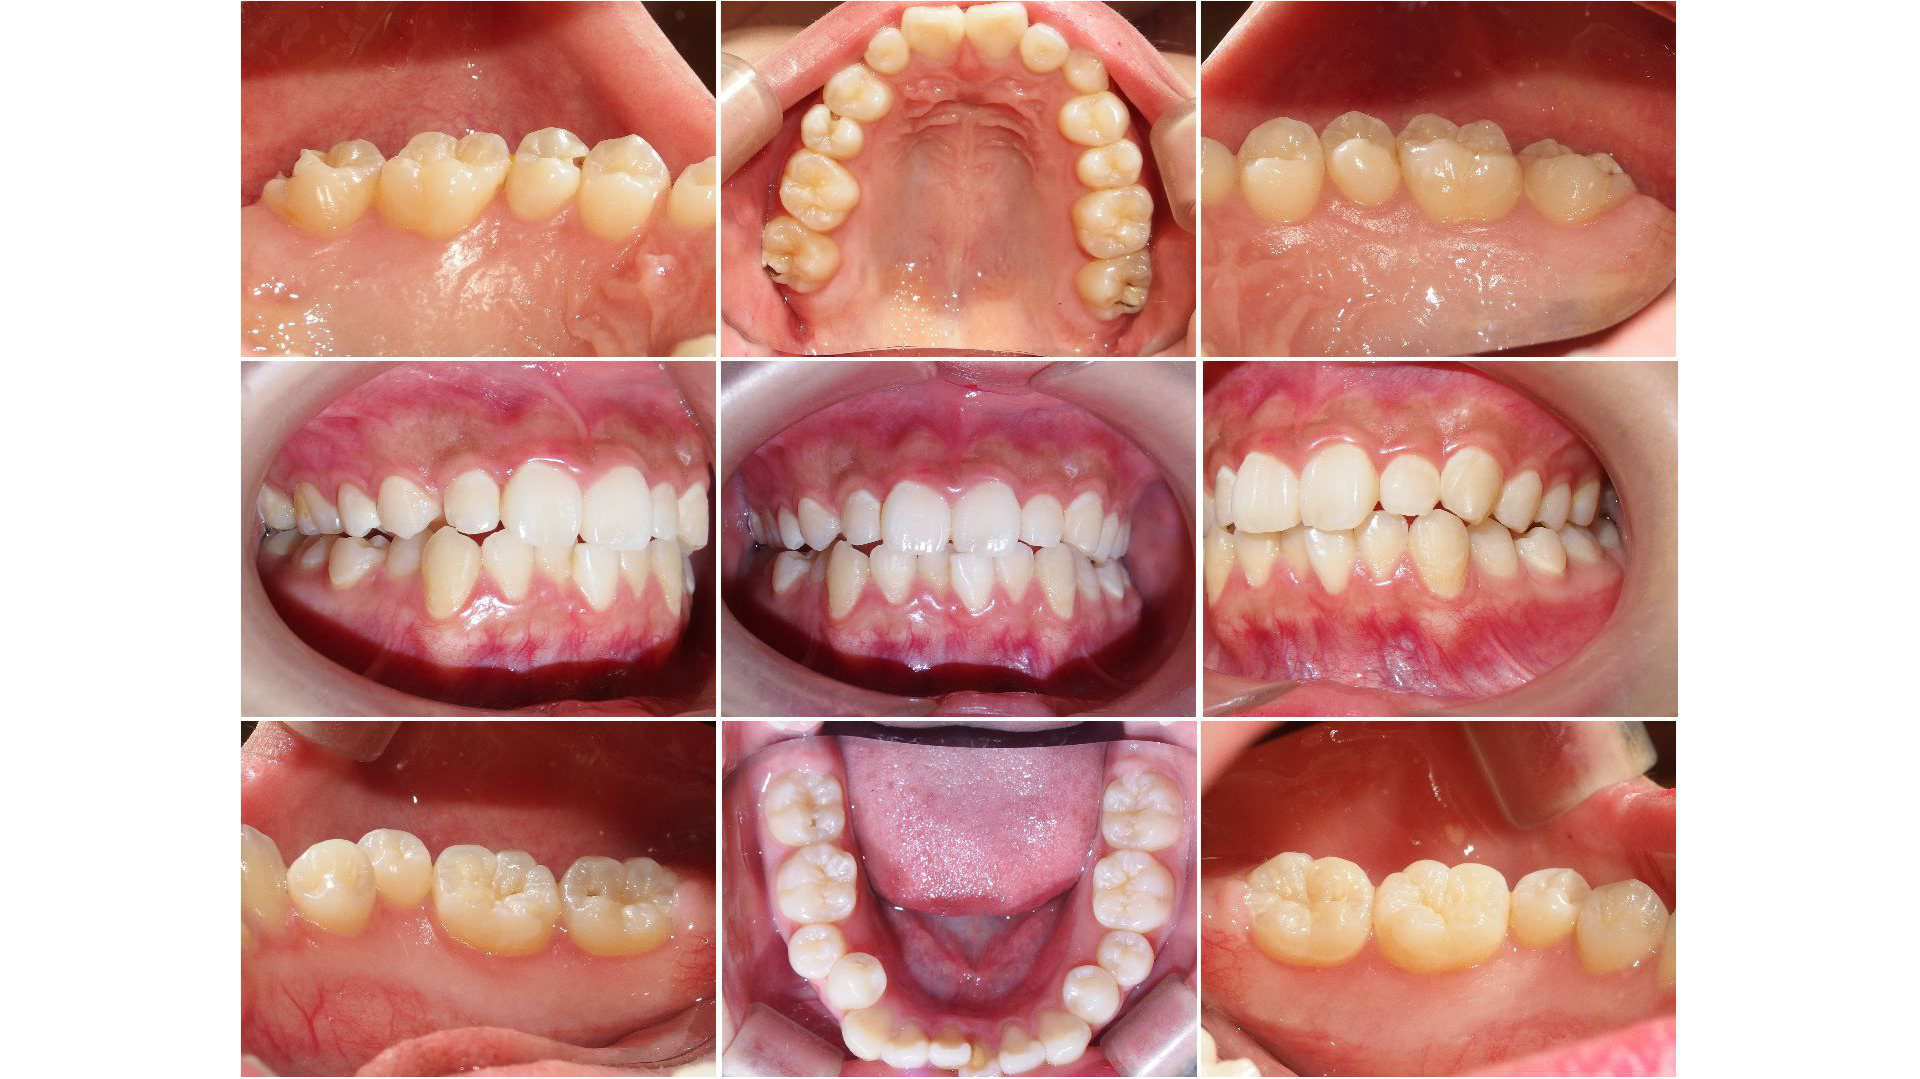

オリエント歯科では、まずはスタートとして、ご自身のお口の中がどういう状態なのかということをお伝えしているようにしています。そのため、受診された方のお口の中の写真を撮らせていただいています。正面から、右側から、左側から、上顎全体、下顎全体、右上、右下、左上、左下と9枚記録させていただくことが多いです。また必要に応じてレントゲン写真を撮らせていただきます。

カウンセリングをするときのパソコン画面イメージです。